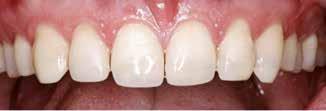

Postoperativ status

okklusal-vertikale dimension. De afficerede dentinoverflader blev ridset i overfladen med en grov diamant, men derudover blev der ikke foretaget nogen form for kavitetspræparation, da intentionen var at gennemføre en minimalt invasiv behandlingstilgang. Kofferdam blev anlagt i hvert arbejdsfelt (Fig. 3) og adhæsivet påført med en æts-og-skyl-strategi (ætsning af emalje og dentin, primer, adhæsiv). Derefter blev tænderne bygget op med en mikrohybrid komposit for at genskabe tandens naturlige form (Fig. 4). I underkæbefronten blev der kun lagt et tyndt lag med komposit pga. pladsmangel. Efter omhyggelig pudsning og polering havde patienten okklusion på samtlige tænder og var tilfreds med både funktion og æstetik.

Fig. 4. Færdigrestaurerede tænder med komposit.

Fig. 4. Final restored teeth with composite.